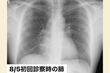

8月5日、「東京都発熱相談センター」で紹介された病院でのレントゲン写真。まだ肺はキレイだった(写真:取材者提供/東洋経済オンライン)

[写真 3/7枚目] 8月5日、「東京都発熱相談センター」で紹介された病院でのレントゲン写真。まだ肺はキレイだった(写真:取材者提供/東洋経済オンライン)